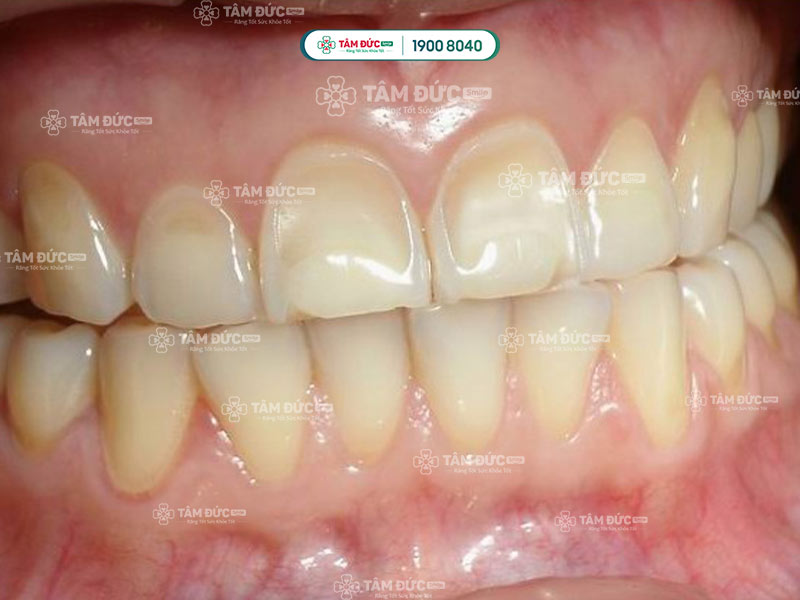

2.2. Răng nhạy cảm do bị mất men răng

Men răng là lớp ngoài cùng của răng, có công dụng bảo vệ răng khỏi các tác nhân gây hại. Khi men răng bị mòn, ngà răng sẽ lộ ra. Ngà răng có chứa các ống dẫn truyền thần kinh, khi các ống này bị kích thích bởi các tác nhân bên ngoài như thức ăn nóng, lạnh, chua, ngọt, sẽ gây ra tình trạng nhạy cảm ở răng.

Mòn men răng là nguyên nhân làm cho răng bị nhạy cảm